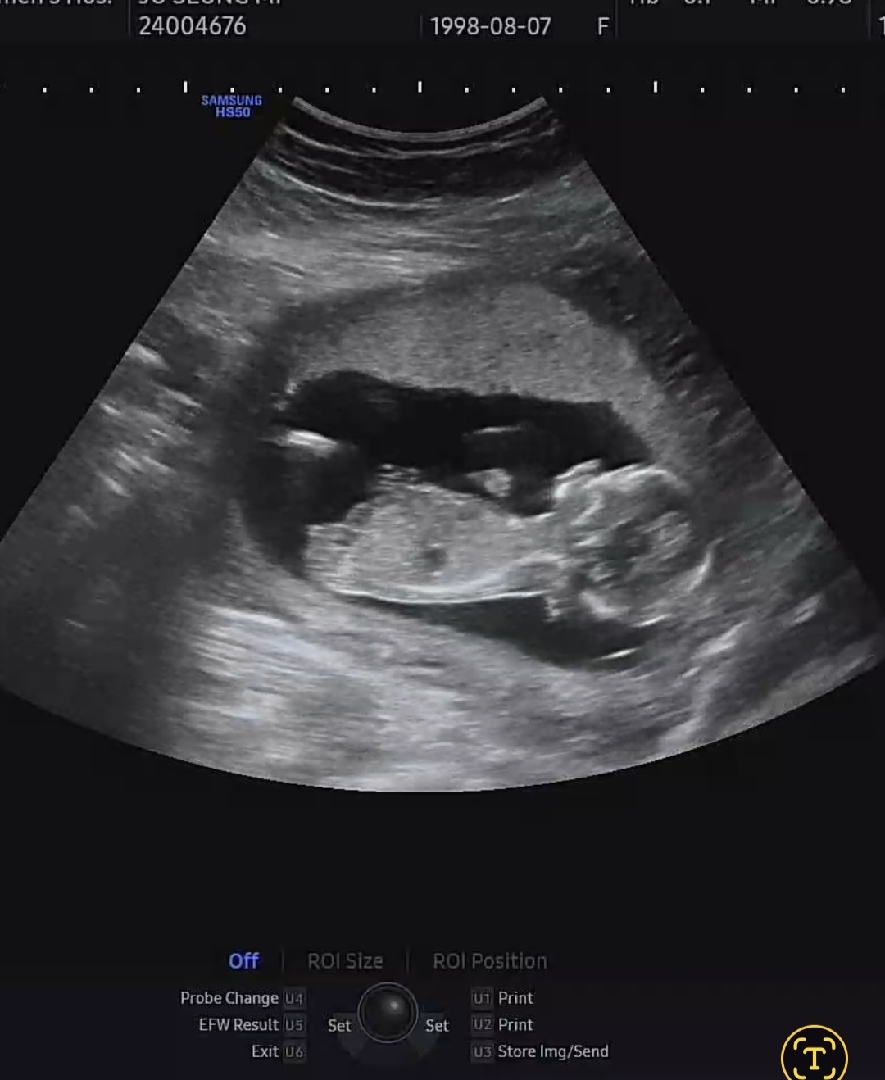

14주6일 각도법 선생님!!!

딸일까요 아들일까요?!?!?!